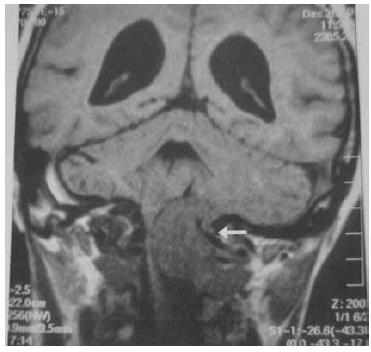

Observe a imagem em corte coronal feita por Ressonância Magnética de crânio, na fase sem contraste.

(Jotz et.al. Tratado de Deglutição e Disfagia no adulto e na criança. p. 257)

Assinale a alternativa que apresenta a avaliação correta da região apontada pela seta branca.